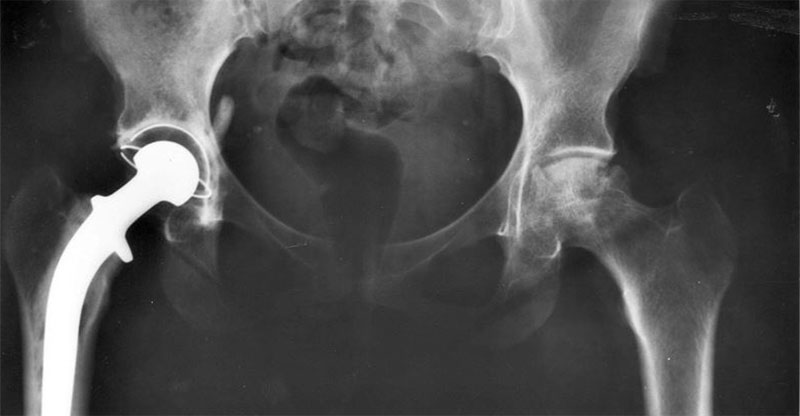

Prótesis de cadera: nuevo abordaje quirúrgico

Esta nueva técnica, a la que se conoce como “abordaje microposterior” es mínimamente invasiva, por lo que se limitan considerablemente las secuelas postoperatorias y las consecuencias propias de la cirugía. Además, al tratarse de una técnica mucho más conservadora que las tradicionales, la recuperación es mucho más rápida, limitando las complicaciones.

Lo más característico de Superpath es que no es necesario desinsertar músculos y la cápsula articular de la cadera se queda intacta en todo momento. Obviamente este hecho es el más importante y el que logra que la recuperación se convierta en algo efectivamente más rápido.

La indicación de la nueva técnica de reemplazo de cadera está indicada para pacientes de 70 años de edad que todavía requieren una actividad física moderada. Las técnicas tradicionales llevan consigo la posibilidad de que una de las complicaciones más temidas, la luxación de la prótesis, termine por retardar la recuperación o requiera intervenciones nuevas para solventar el problema. No obstante, mediante la nueva intervención esto está descartado, ya que se mantiene intacta la cápsula de la articulación, que funciona como soporte para la prótesis que se ha colocado. La intervención Superpath también elimina secuelas típicas del reemplazo de cadera como la dismetría entre las extremidades.